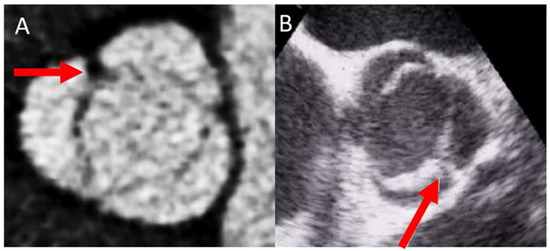

2. Diagnosis and BAV Phenotype

4.1. Valve Calcification